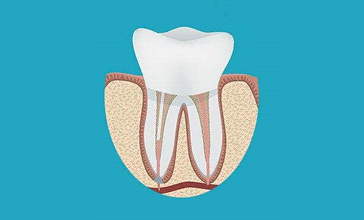

Anatomy of a Tooth

To understand root canal treatment, it is crucial to understand the structure of a tooth. A tooth is composed of three main parts: the enamel, dentin, and pulp. The enamel is the hard, outer surface that protects the tooth. Beneath the enamel lies the dentin, a softer layer that supports the enamel and carries nerve fibers. At the center of the tooth lies the pulp, which contains nerves, blood vessels, and connective tissue. The pulp extends from the crown of the tooth to the tip of the roots in the jawbone.